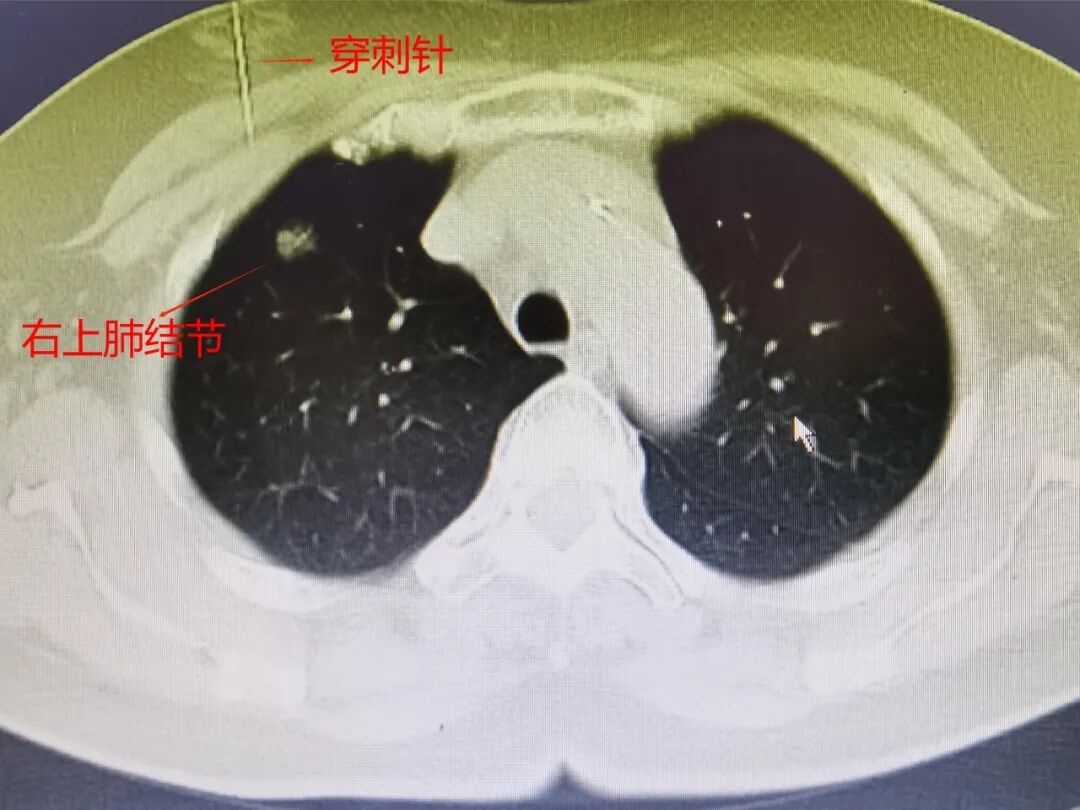

手術(shù)當天一大早,胸外科醫(yī)師護送趙阿婆來到CT室。在CT引導下,采取局部麻醉,相對比較表淺的右上肺結(jié)節(jié)使用穿刺針刺入肺表面后注射亞甲藍染色標記,左上肺偏深稍大的結(jié)節(jié)使用肺穿刺定位針,將定位針尖端勾住結(jié)節(jié)周圍肺組織。